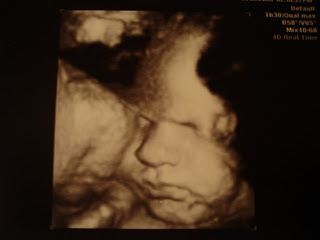

(The pictures are a lot better quality in original form, but I had to take a picture of a picture with our camera since we don’t have a scanner.)

Similiar picture in black and white! I think this little guy is going to look like Ty too!!